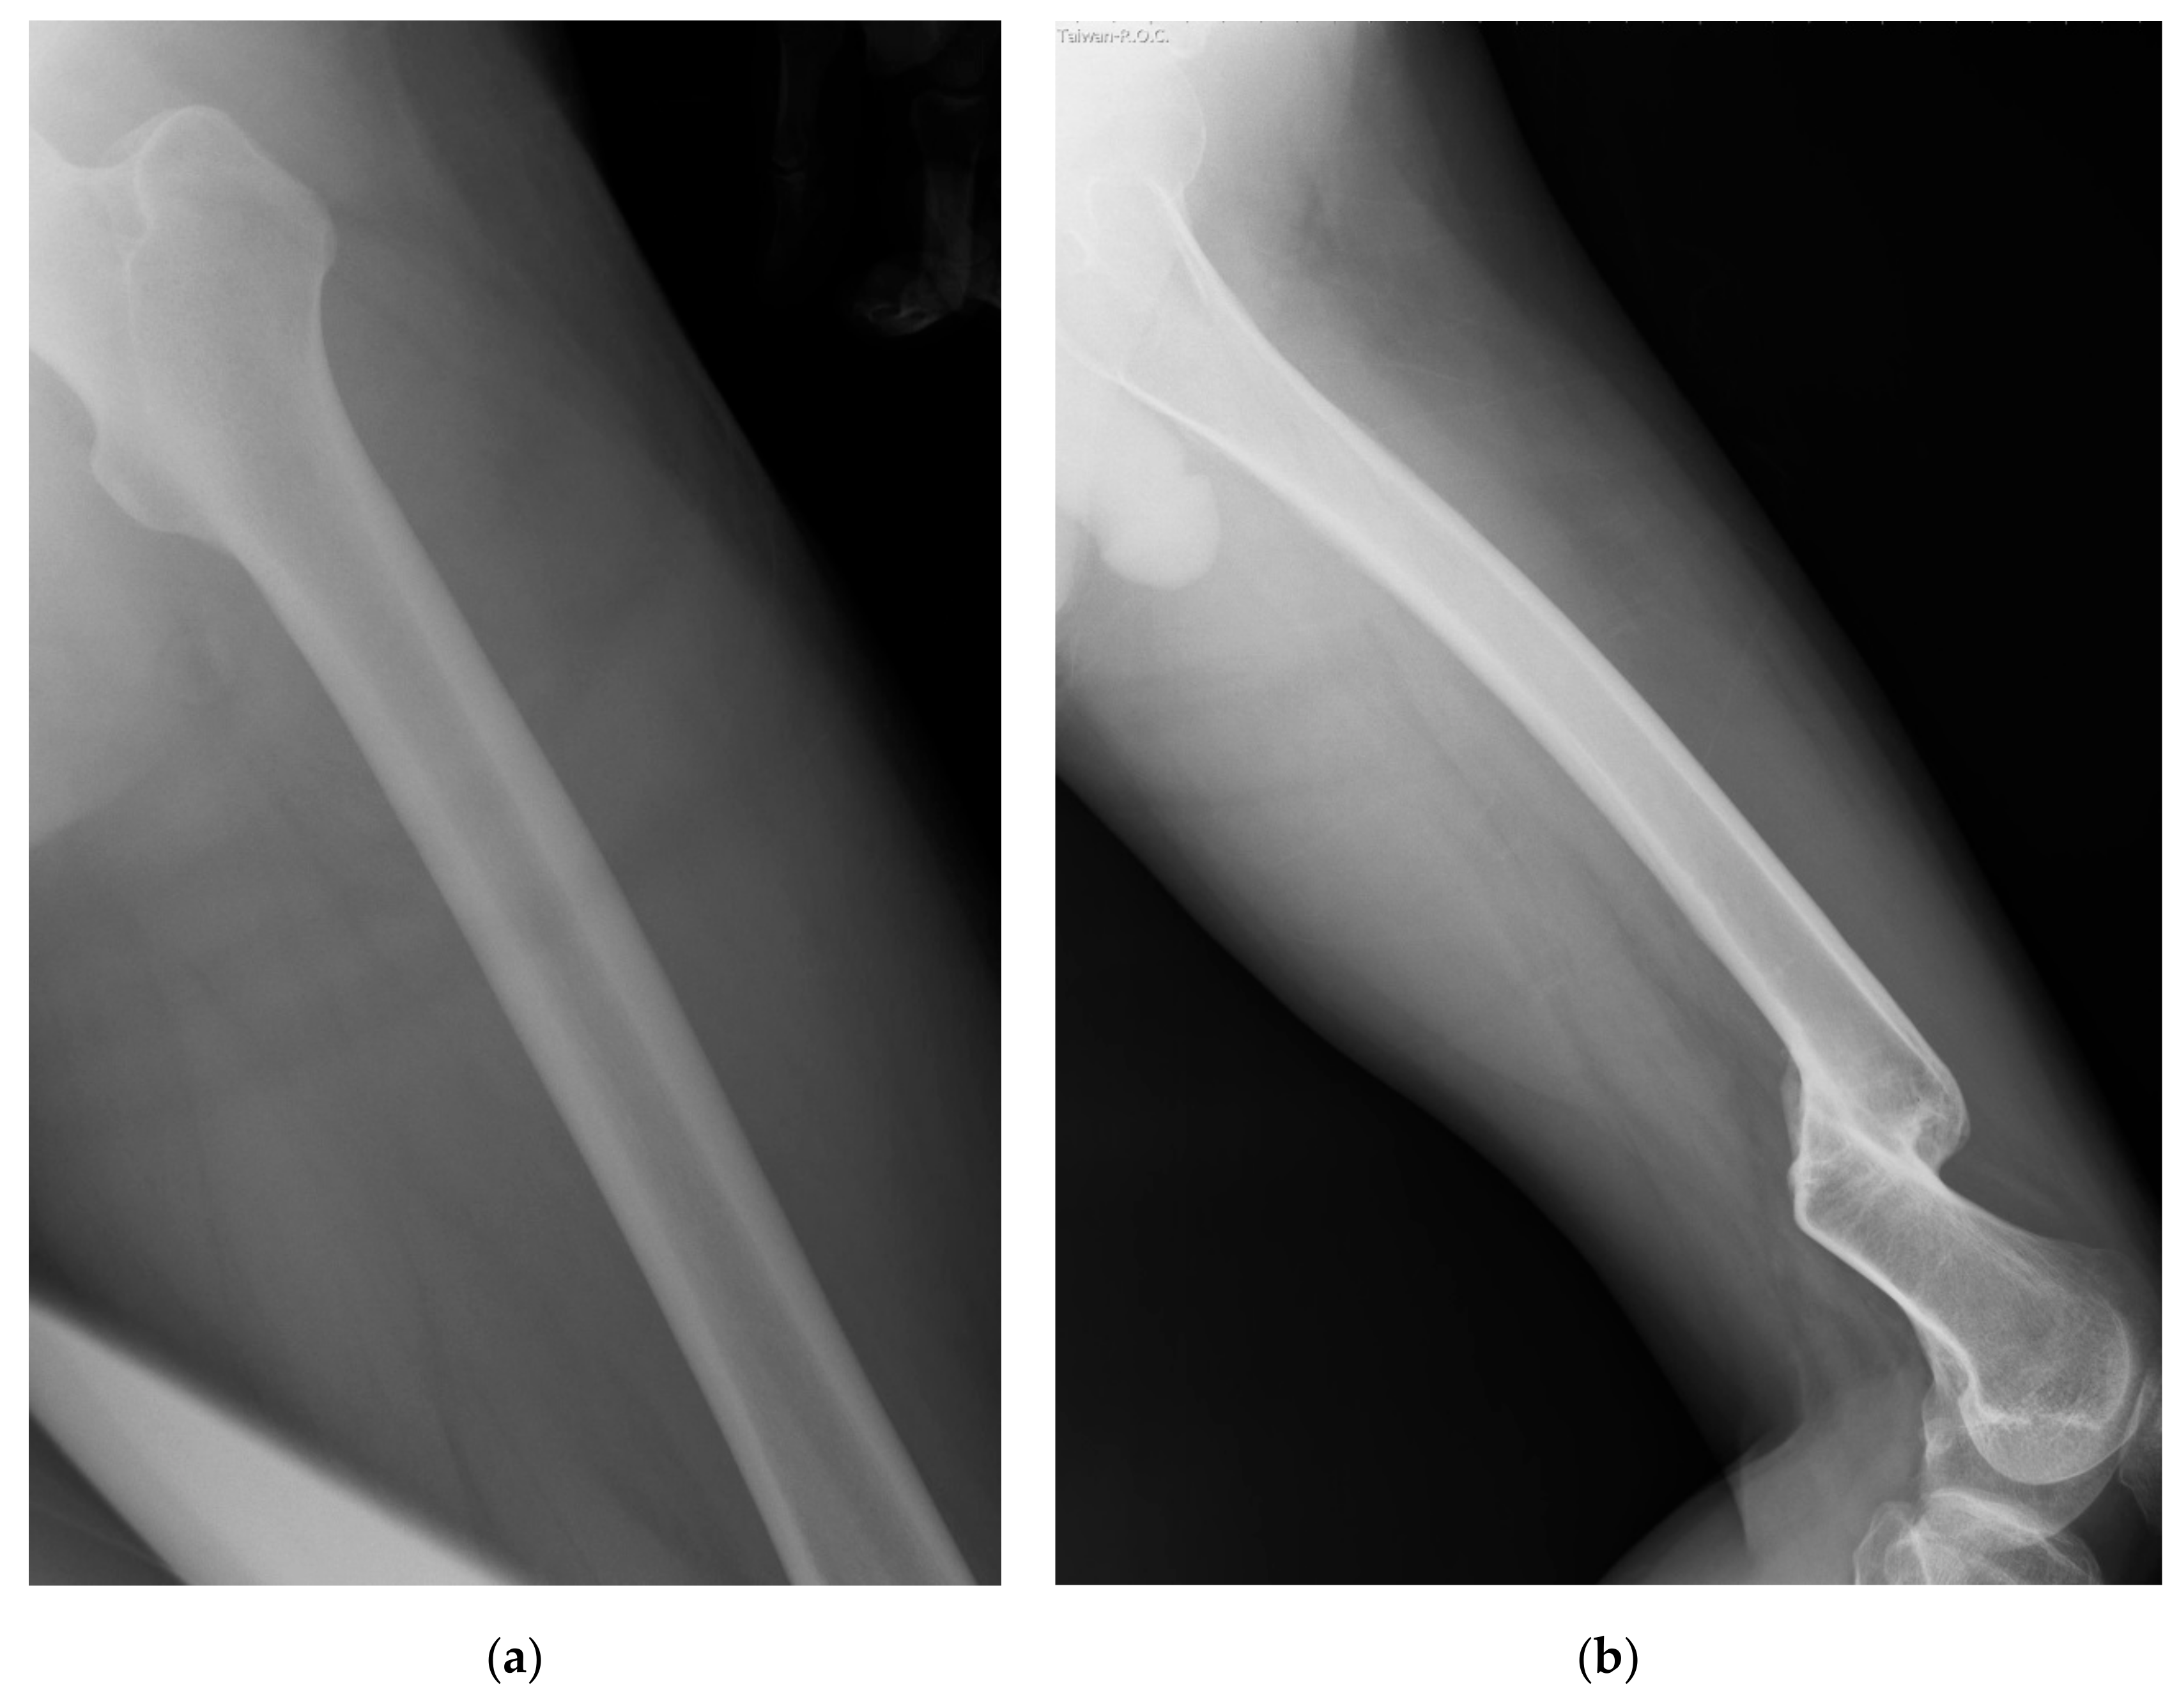

After the image was read into the program, we determined the proximal and distal ends of the femoral shaft outline and the medullary canal. Then we drew the upper and the lower border of both the femoral shaft outline and the medullary canal between the proximal end and the distal end. Because the femur is in oblique position in the lateral view of the radiography, we regarded the anterior and posterior sides as the upper side and lower sides, accordingly. For the femoral shaft outline, the distal ends of the upper and lower borders were defined as the junctions of the femoral shaft and the condylar region on both sides (Figure 3 blue points 1 and 2). After we got the two distal ends, we drew a line between them. The junction of this line and both borders of the medullary canal were defined as the distal end of the border of the medullary canal (Figure 3 yellow points a and b).

The proximal end of the lower border of the femoral shaft outline was defined as the bottom of the lesser trochanter (Figure 3 blue point 3). After we got this point, we drew a line through this point and measured both angles of this line and both borders of the femoral shaft outline. When these two angles were equal, the point of intersection of this line to the upper border of the femoral shaft outline was defined as the proximal end of the upper border of the femoral shaft (Figure 3 purple point 4). The intersections of this line to both the upper and the lower borders of the medullary canal were defined as the proximal ends of both borders of the medullary canal (Figure 3 yellow points c and d).

Figure 3. Blue points 1 and 2 were marked as the distal ends of cortical border (femoral shaft outline). Blue point 3 was marked below the lesser trochanter. Purple point 4 was determined on the other side. Both points 3 and 4 were the proximal ends of cortical border. The 4 yellow points were the distal and proximal ends (a, b and c, d) of borders of the medullary canal.